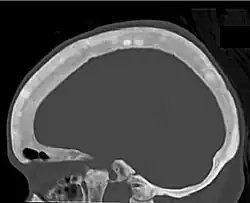

CT shows focal areas of osteosclerosis.[18] -

CT scan of the same case.[18]